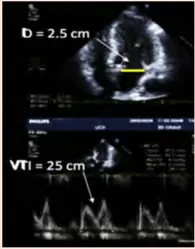

- Measurement of the AR peak velocity and VTI by CWD allows calculation of the EROA and RVol

- The threshold for severe AR is an EROA ≥0.30 cm^2 and an RVol > 60 mL